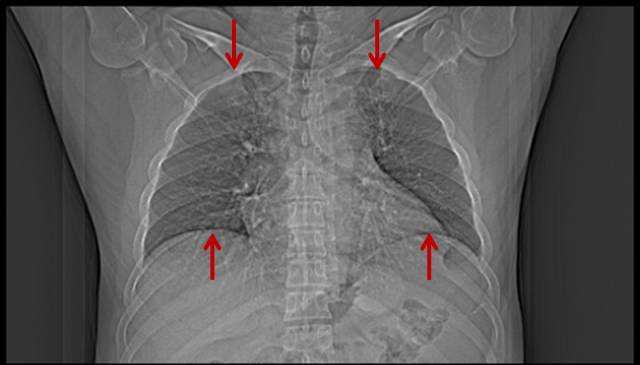

吸烟导致双肺坠积效应

男,47岁,吸烟者,每天2盒。

图片

图4

轻度肺坠积效应,这部分肺无法执行换气功能,属于亚临床患者,重度才有自觉气短症状(详细请点击→吸烟者的肺,看完果断戒烟吧!